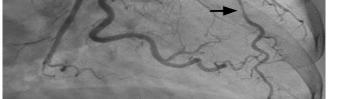

Unfortunately, there were no previous labs available for comparison. An electrocardiogram (ECG) was performed (Image 1), as well as a portable chest radiograph (Image 2). The patient was placed on a non-rebreather mask at a rate of 10 liters per minute.

Image 1. Electrocardiogram of a 44-year-old man with hemoptysis and hypoxemic respiratory failure showing sinus tachycardia with an incomplete right bundle branch block, left ventricular hypertrophy, possible left atrial enlargement, and marked ST abnormality, concerning for lateral ischemia.

An ECG may similarly hold suggestive value but is ultimately unlikely to determine the etiology of a patient’s hemoptysis. This patient demonstrated sinus tachycardia with an incomplete right bundle branch block along with left ventricular hypertrophy (LVH) and possible left atrial

enlargement. Tachycardia and right heart strain again suggest the possibility of pulmonary embolism, while the left atrial enlargement might suggest mitral valve stenosis as the cause of the hemoptysis. However, no murmur was noted on exam, thereby decreasing the probability that he had significant stenosis of the mitral valve, and pulmonary embolism should not cause diffusely abnormal lung sounds as were heard in this patient. Left ventricular hypertrophy could hint at congestive heart failure, although this is a rare cause of hemoptysis and even rarer for it to present so severely.